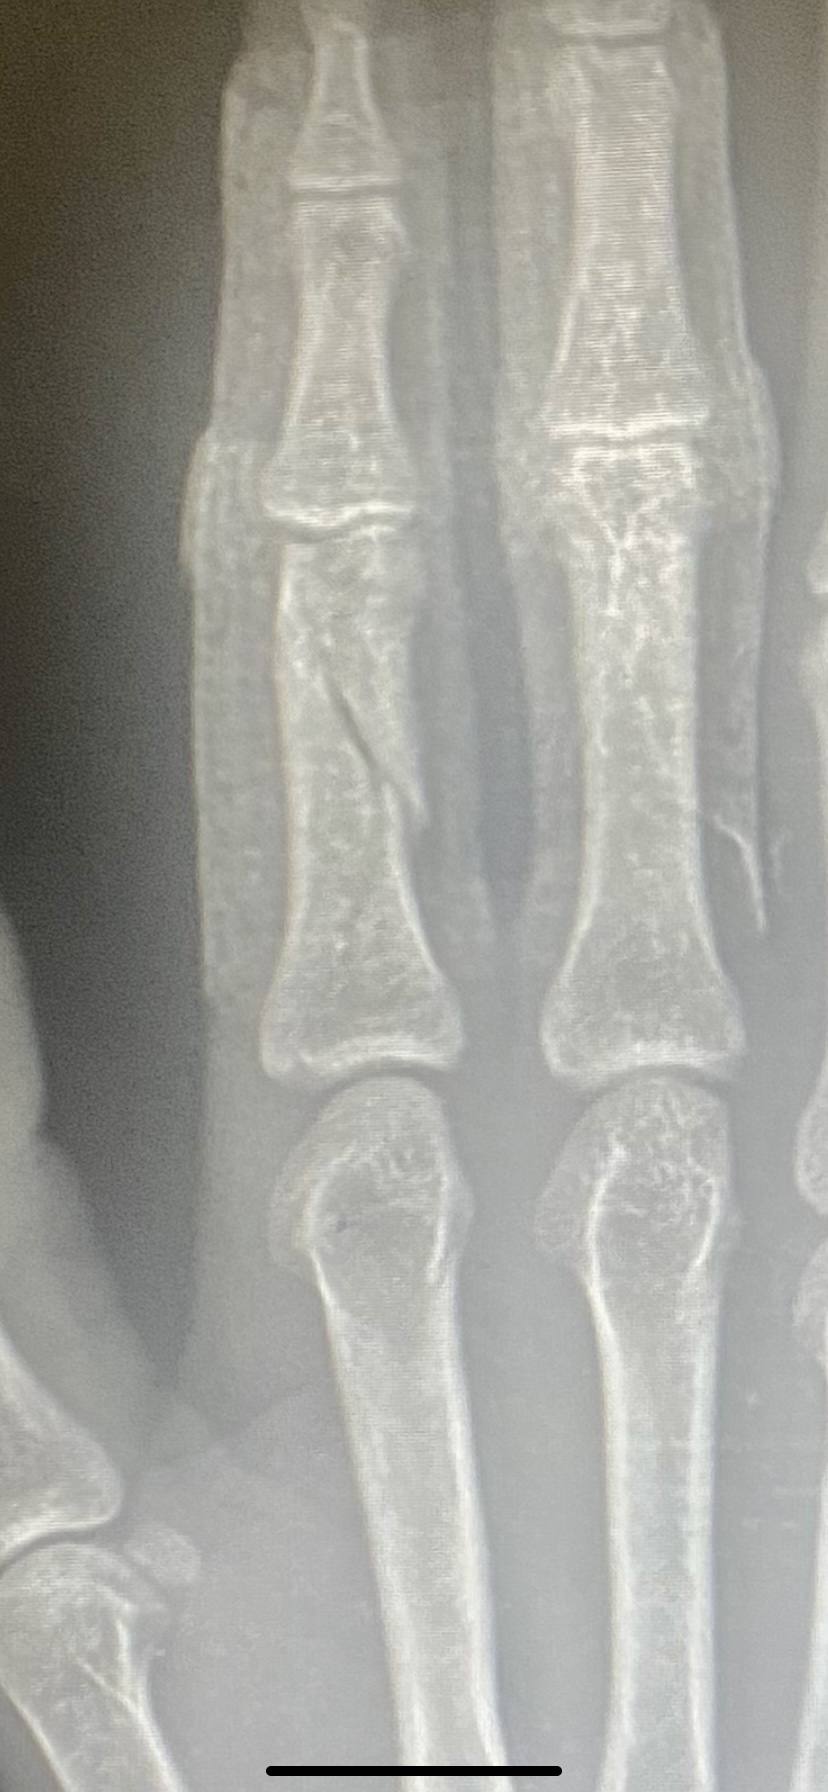

Index finger fractured.. Tepping done by doctors.

2 weeks baad bhi same xray aaya... kuch difference nhi he...

kya bone sahi jagah par he?

thik hone me kitna samay lagega..?